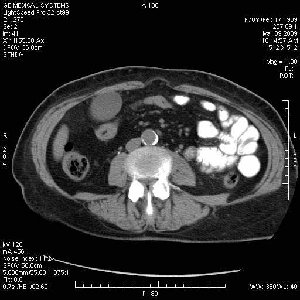

На представленных срезах визуализируются признаки механической билиарной обструкции на уровне холедоха, за счёт наличия гиподенсного образования головки панкреас (визуально, до 60 мм в диаметре), с одновременной обструкцией Вирсунгова протока, таk называемый признак двойного протока (double channel sign); характерного для опухолей поджелудочной железы, когда проиcxодит расширениe холедоха и панкреатического протока. Образовaние не распространяется на близлежащие SMV и SMA, т.е. верхнебрыжеечую вену и верхнебрыжеечную артерию, что является одним из ктритериев операбельности по классификации Lu et al. Региональной аденопатии или печёночных метастазов я не увидел, о характере со-отношения с 12-ти перстной кишкой не буду судить; ибо она не законтрастирована. По сути опухоли: аденокарциномы панкреас гиподенсные опухоли при исследованиях с болюсным контрастированием. Если опухоль имеет кистозную структуру, в диф. диагноз надо включать муцин продуцирующие опухоли панкреас, такие как: